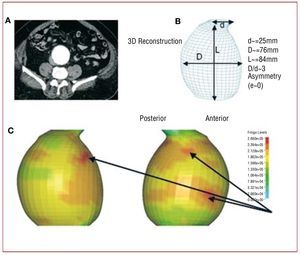

Calculating the risk of rupture requires measuring the tensile stresses on the aneurysm wall and knowledge of the corresponding stress failures. Thus, it is clear that this is an area where computational and experimental solid and fluid mechanics could genuinely contribute to the better management of this disease. Over the last 10 years, there have been a large number of studies aimed at modeling flow-structure interaction in idealized geometries of aneurysms as well as in 3D reconstructions of aneurysms obtained from CT scans or other medical imaging techniques.123-129 The results of these studies represent a great improvement over the population-based statistical criteria currently used in the clinical setting. For example, they have shown that the wall tensile stresses depend on the specific curvatures and asymmetries of the aneurysm wall. Wall tension was found to be greater on the flatter surface (which would typically correspond to the posterior surface of an AAA due to the presence of the spinal column) and at the inflection points of the bulge (where the surface curvature changes from concave to convex). These results are consistent with the fact that a large number of AAA rupture in the posterior part of the side wall (Figure 8). In addition, these computational studies have shown that even though the presence of the intraluminal thrombus has great biochemical effects on the further degeneration of the wall, the observed re-channeling of the blood flow leads to a dramatic reduction in wall tension providing a protection mechanism against rupture. Figure 8 shows the values of Von Mises stresses along the aneurysm wall indicating the most likely locations of rupture. The Von Mises criterion is a formula for combining the 3 stresses at any location of the wall into an equivalent stress, which can then be compared to the yield stress of the material to determine the risk of rupture. Figure 8 shows that in both symmetric and nonsymmetric cases with varying degrees of dilatation and eccentricity, the intraluminal thrombus leads to marked reductions in Von Mises stresses and therefore of the risk of rupture.

Figure 8. Effect of the intraluminal thrombus (ILT) in reducing the risk of rupture. (A) Von Mises stresses in the wall of an abdominal aortic aneurysm (AAA) for the case of no ILT, and for the cases when the ILT occupies 40% and 80% of the enlarged volume of the arterial lumen. Note that the maximum values of the stresses (calculated at peak systole) are not only reduced in the presence of the ILT, but also that their location shifted to the neck. (B) Reduction in the value of the maximum Von Mises stresses with the % of volume occupied by the ILT for a symmetric AAA (top part) and nonsymmetric AAA (bottom part). The stresses have been normalized using the value in a healthy aorta. Adapted from Tang et al.214

To precisely calculate the wall tension (Von Mises stresses) throughout the entire aneurysm in each patient-specific case, the following are required: a) a precise description of the 3D geometry of the aneurysm wall; b) the 3D geometry of the intraluminal thrombus (if present); c) more importantly, the values of the wall thickness throughout the entire aneurysm; and d) mathematical models that characterize the nonlinear anisotropic biomechanical properties of the tissue at each location along the wall. The accuracy of the computed wall tension distribution shown in Figure 9 depends on how rigorously these 4 components are defined in the analysis. Although the setting of the proper initial and boundary conditions, and the relatively complex shape of the elastic walls present some difficulties when computing the flow, the real shortcomings arise from the current inability of the various medical imaging techniques to provide precise information not only on wall geometry, but more importantly, on the precise composition and structure of the wall at each location, and therefore of its mechanical properties, including yield stresses. Yield stress, considered as the failure stress of the aneurysm wall, is unfortunately an unknown property of the material. This is due to the fact that, after enlargement of the vessel, the wall undergoes remodeling and in most cases its composition is unknown. The reduced ability of current numerical analysis to compute the precise distribution of tensional stresses in the aneurysm wall has motivated many researchers to look into surrogate methods to determine the risk of rupture. The purpose of all these studies is to find robust correlations that link specific features of its geometry or particular features of the flow with rupture, and which could provide a better criterion than the current one which is based solely on maximum diameter.130,131

Figure 9. Von Misses stresses calculated along the wall of a reconstructed model of an abdominal aortic aneurysm (AAA) of a 75-year-old male patient. (A) Slice of a computed tomography (CT) scan showing the cross-section of an AAA 6 cm in diameter without any intraluminal thrombus. (B) 3D reconstruction of the AAA from the CT scan frames. The distance between two consecutive CT sections was 0.75 mm. (C) Left and right view of the aneurysm showing that the maximum value of the von Misses stresses on the wall are along the side and in the posterior region of the aneurysm.